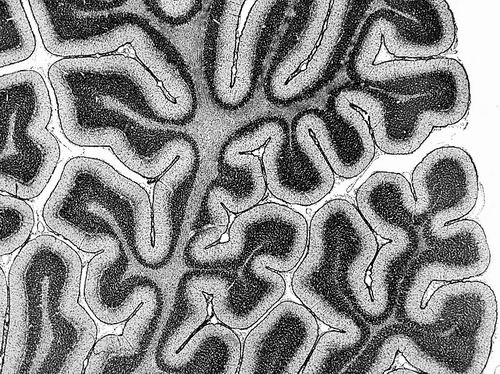

首张大脑组织结构图谱问世

随着人的成长,大脑中协同工作的区域会发生变化。

大脑是一个“吵闹”的地方。有时两个相距甚远的大脑区域会同时活跃,表明它们在协同工作以支持相同的功能。这些区域被认为是“功能性连接的”,尽管它们在大脑中未必相邻。